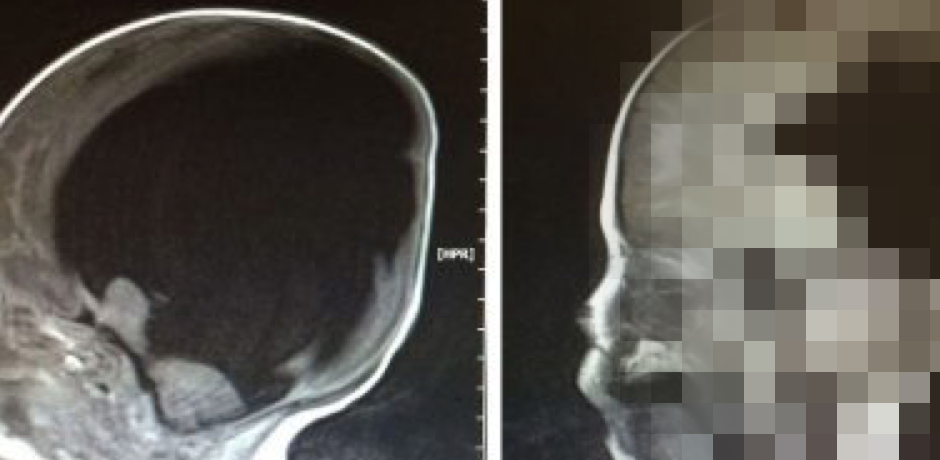

Снимки головного мозга младенца показывали, что огромные объемы спинномозговой жидкости сильно нарушили развитие тканей головного мозга. С такими повреждениями ребенок был практически обречен на бездумное, растительное существование.

Новые снимки головы ребенка показали неслыханное.

Судя по всему, его мозг сам постепенно пришел в норму!